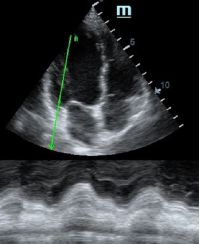

Оценка кооптации нижней полой вены ещё никогда не была такой простой и точной, никаких лишних деталей, просто устанавливаем клипер по анэхогенному участку.

Оценка сокращения сегментов левого желудочка на глаз постепенно уходит в прошлое. Если в приборе нет функции радиального или лонгитудинального стрейна, на помощь опять может прийти Free Xros. Утолщение более 5 мм в систолу – нормальное сокращение, 2-5 мм гипокинез, истончение в систолу – дискинез.